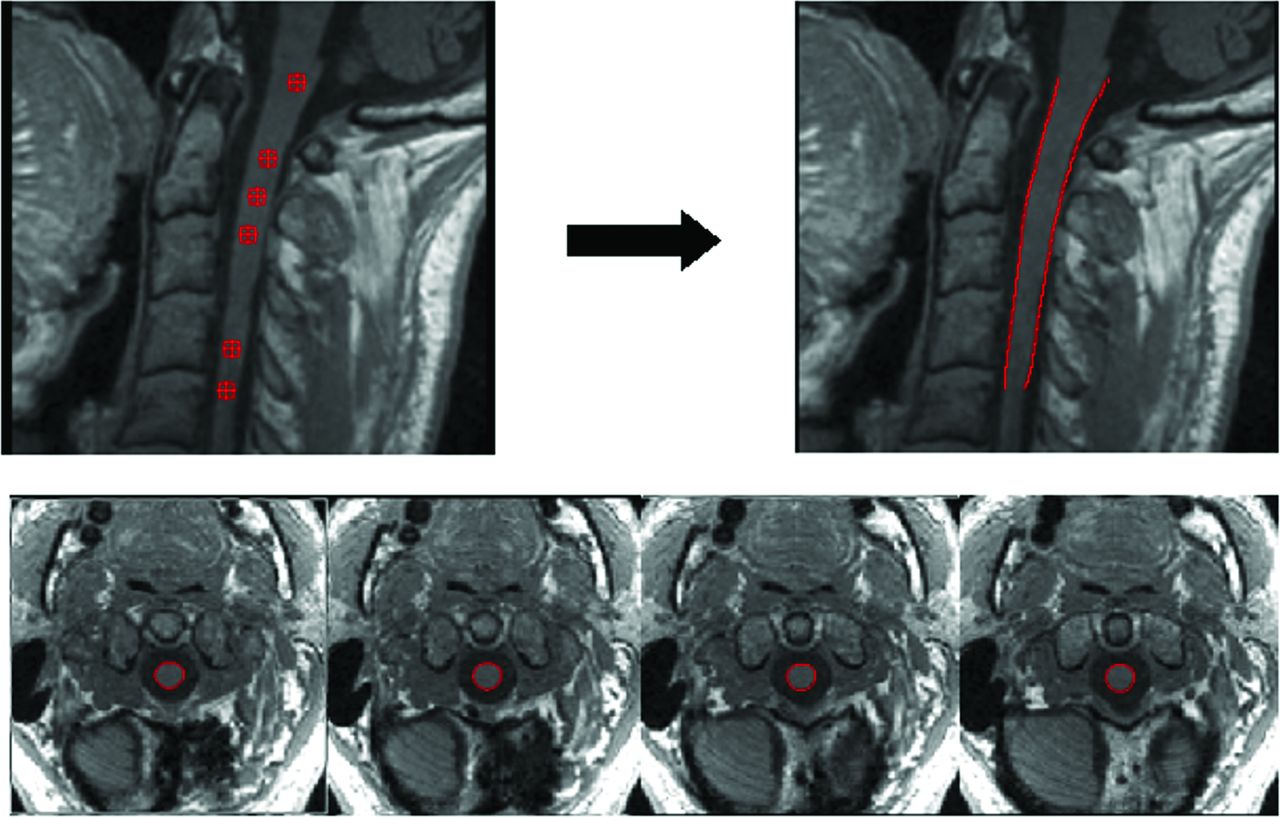

Cross-sectional area measurements were assessed using a semiautomatic segmentation method based on an active surface model of the cord surface with intrinsic smoothness constraints,18 provided in the Jim 6.0 software package (http://www.xinapse.com/home.php). Briefly, the sagittal 3D T1-weighted scans of the cervical cord from each patient were first reformatted in the axial plane and resampled to 1-mm section thickness. Then, the active surface method was applied to each scan to estimate the cord surface and cord centerline (Fig 1). An initial estimate of the cord centerline was manually provided by placing landmarks at the extremes of the cord region to be studied and at approximately each 10 mm between these landmarks. Thus, the region studied comprised the segment from the most cranial section in which the odontoid process was visible down to the C5 superior margin. A single operator placed all landmarks. The cord centerline and cord outlines at each section were calculated using a segmentation algorithm, with steadily increasing refinement of the active surface model describing the cord outline. The total cord length was calculated in each region as the distance along the centerline between the upper and lower landmarks. In each region, the mean cervical cord CSA was calculated as the total cord volume divided by the cord length, and CSA was also measured at the C2–C3 (CSA23), C3–C4 (CSA34), and C4–C5 (CSA45) discs. CSA measurements were then normalized (NMCSA, NCSA23, NCSA34, NCSA45)—in a manner similar to the proposal of Lin et al21—to the intracranial cross-sectional area measured at the inferior margins of the corpus callosum in an axial slice of the proton density–weighted image of each patient, as previously suggested.18 This adjustment was performed because cranial size was found to significantly correlate with the cord area in healthy controls.22 In addition to the normalized CSA measurements, the annualized (normalized) CSA loss rates between the baseline and follow-up examination (aNMCSA, aNCSA23, aNCSA34, aNCSA45) were also evaluated.

An example of the cord surface estimation obtained using the active surface method. The upper left image shows the location of the landmarks (red markers) that can be visualized in this sagittal slice. These landmarks were manually placed in the axial slices at the center area of the cord with a distance between them of approximately 10 mm. The upper right image shows the cord outline estimation (red lines). The lower axial slices show some examples of the spinal cord segmentation obtained (region within red contour).